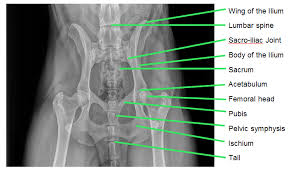

A non articular depression portion of the acetabulum used for the attachment of the ligament of the head of the femur. The canine pelvis shape from a ventral view resembles a rectangle. The three components of each hip bone are the ilium, pubis and ischium. A non articular depression portion of the acetabulum used for the attachment of the ligament of the head of the femur. Anatomy of the male canine abdomen and pelvis on ct imaging.

The three components of each hip bone are the ilium, pubis and ischium. It provides information about a dog's skeletal, reproductive, internal, and external anatomy, along with accompanying labeled diagrams. However, dogs don't have a collar bone, unlike humans; It has the ability to flex extend rotate adduct and abduct its whole limb because of this. With the large range of breeds and dog sizes, despite their difference in appearance, it might be surprising to hear dog anatomy is generally the same with regards to physical anatomy and characteristics. The pelvis is firmly attached to the spine (sacroiliac joint) and the limb is longer and more angulated than the thoracic limb (which is designed to bear weight and absorb impact). The acetabulum provides the socket to the joint of the hip and is composed of all three bones of the pelvis. Muscles of the pelvic limb.

The hindlimb skeleton of the canine includes the pelvic girdle, consisting of the fused ilium, ischium, and pubis, and the bones of the hindlimb. Types and functions of dog anatomy This is a really nice video tour of the hip and pelvis, and even though it talks about the human hip, the anatomy is very similar in the dog. The detailed structure depends on a lot of factors such as the dog breed, age, and weight. Secure the dog's pelvic limbs in this position using tape around the femurs at the level of the stifle joint (figures 2a and 2b). It has the ability to flex extend rotate adduct and abduct its whole limb because of this. The girdle musculature and the rump muscles. Urogenital system of the dog the pictures in this section are reprinted with permission by the copyright owner, hill's pet nutrition , from the atlas of veterinary clinical anatomy. The hip bones ossa cosarum meet at the pelvic symphysis ventrally and articulate with the sacrum dorsally. Muscles of the pelvic limb. Anatomy is a branch of biology and medicine that studies the morphology and structure of living organisms. By means of roentgenological and morphological methods in 100% of cases, lateral, iliac and hypogastric ln are revealed. A non articular depression portion of the acetabulum used for the attachment of the ligament of the head of the femur.